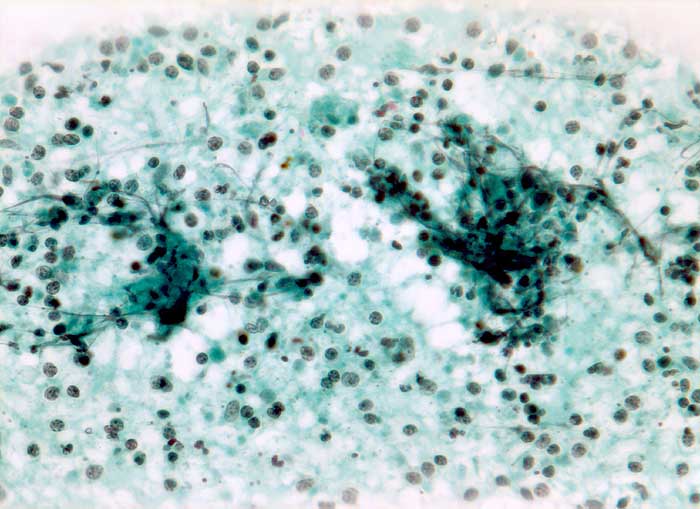

PathoPic – image database / PathoPic ID 5514 - Tuberkulose

Tuberkulose

Entzündung infektiös

Lymphknoten, Kopf-cervikal

Feinnadelpunktion Lymphknoten submandibulär: Die nicht sehr zellreichen Ausstriche enthalten Detritus vermischt mit neutrophilen Granulozyten und Kerntrümmern.

Fibrin (+) Blutbeimischung + Granulozyten + Lymphozyten (+) Histiozyten (+) Histiozytäre Riesenzellen (+) Plattenepithelien ++ Parakeratotische Plattenepithelien ++

Generalisierte Lymphadenopathie, Stomatitis, HIV positiv.

Zytologische Diagnose: Ausgeprägte granulozytäre Entzündung. Keine Malignitätszeichen.

Zytologie

320